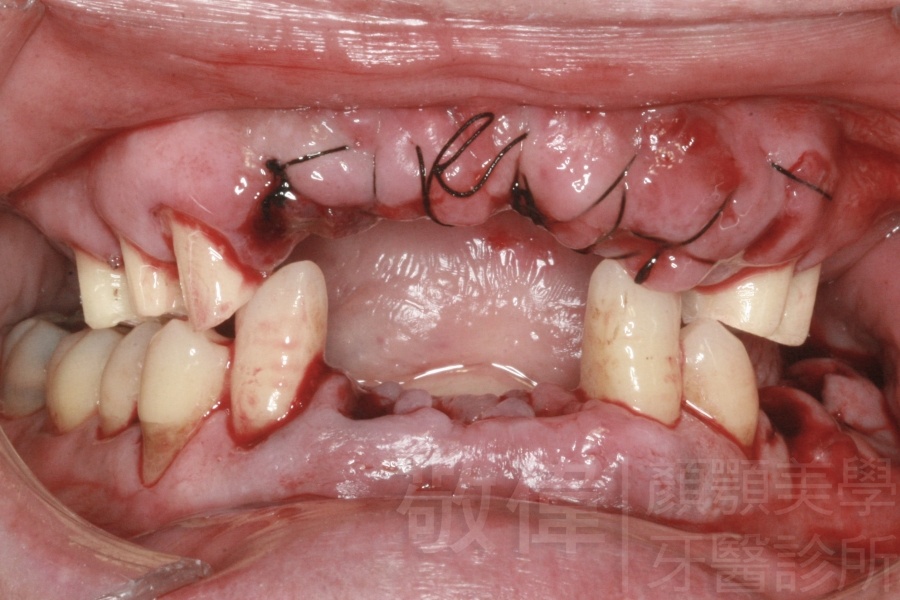

嚴重牙周病   拔除牙周病牙齒